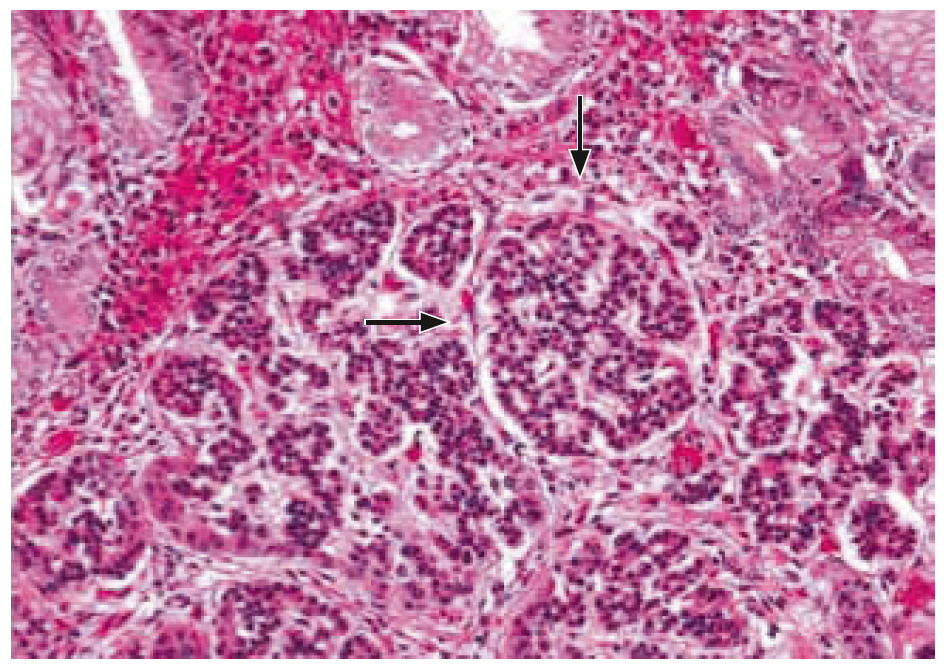

1. Fig. 1. Autoimmune gastritis. Stained with hematoxylin-eosin [5]. | |